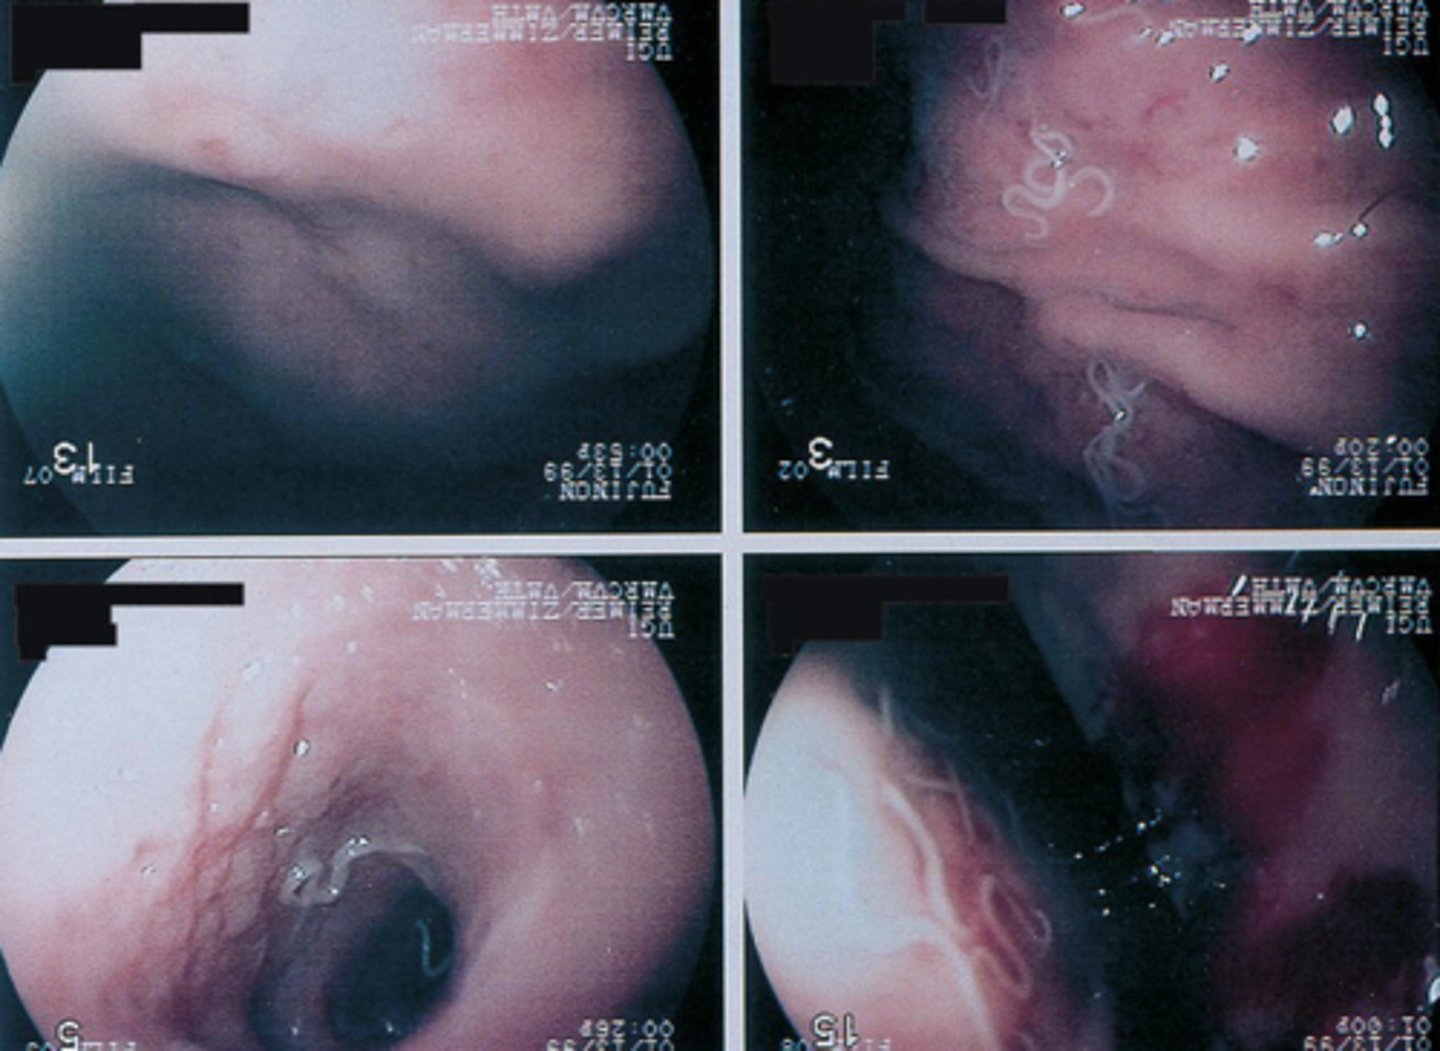

Physaloptera spp. (Stomach worm) (adult)

Which parasite is P if it is from a cat

What parasite is this if it is from a dog

What parasite is this if it is from a cat